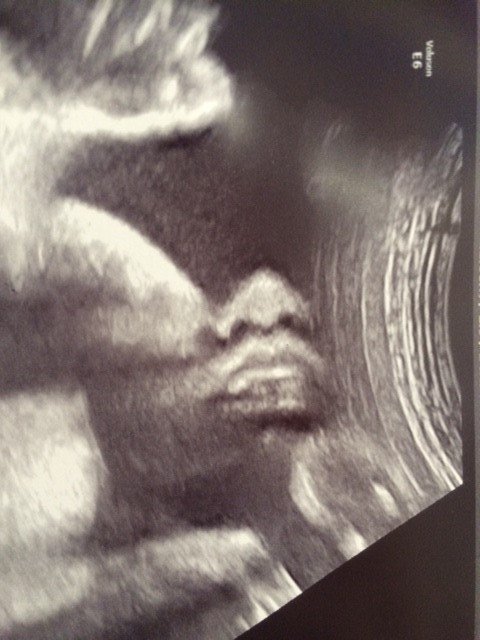

不妊治療って具体的に何するの?~私の妊活体験から~

子育て

妊活